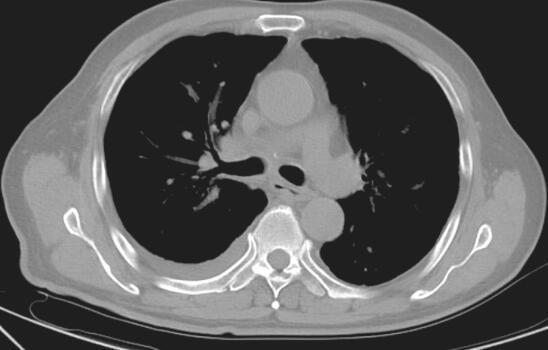

2014年5月2日出现发热、肝功能损伤,停抗结核药。完善胸部CT检查发现右侧胸腔积液,给予抽液检查,胸腔积液常规:颜色:黄色,透明度:清澈,蛋白定性:阴性,白细胞计数:2.6,多个核细胞:5%,单个核细胞:95%。于2014年5月12日调整抗结核药物为HRE。4个月后复查胸部CT(图3和图4)见右肺病灶明显吸收,纵隔淋巴结未见肿大。

图4 2014年9月17日胸部CT

纵隔窗见纵隔,肺门未见淋巴结肿大